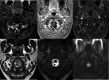

Intradural extramedullary foramen magnum enhancing lesions may be due to meningioma, nerve sheath tumor, aneurysm, or meningeal disease. In this clinical report of 14 patients, we describe a novel imaging finding within the foramen magnum that simulates disease. The lesion is hyperintense on 3D-FLAIR and enhances on 3D gradient-echo sequences but is not seen on 2D-TSE T2WI. It occurs at a characteristic location related to the posterior aspect of the intradural vertebral artery just distal to the dural penetration. Stability of this lesion was demonstrated in those patients who underwent follow-up imaging. Recognition of this apparently benign lesion may prevent unnecessary patient anxiety and repeat imaging.